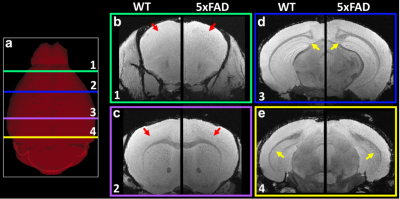

Figure 1 shows the representative T2*-weighted image of both WT (B6) and AD (5xFAD) mice. Compared to the B6, there are numerous hypointensity signals in the cortex region and hippocampus region (red and yellow arrows). These hypointensity areas are likely beta-amyloid plaque deposition. To validate the MRI findings, the QSM results were compared with beta-amyloid plaque staining (Figure 2). The plaques detected by QSM correlated well with the conventional histology in the cortex region. The plaque loading showed no significant difference between QSM and histology (p = 0.087). Figure 3 showed the beta-amyloid plaques detected by QSM and T2*. Compared to QSM, the plaques in the cortex and hippocampus (yellow and green arrows) are barely visible in the T2* map. Due to the long readout, we limited our MGRE scan with only 2 echoes in the current study. With the same limited number of echoes, QSM is better to detect the beta-amyloid plaques than T2*. To further explore the regional plaque deposition in the cortex region, we have divided the cortex area into 41 region-of-interests (ROIs). Figure 4 demonstrated the plaque loading in the whole cortex region of different mouse groups (5xFAD, 5xFADM28L, and 5xFADP522R). Compared to 5xFAD mice, the plaque loading is higher in the cortex region of 5xFADM28L (white arrows). The M28L is a risk variant of AD, which may increase the plaque loading. Compared to 5xFAD mice, the plaque loading is slightly lower in the cortex region of 5xFADP522R, probably because the P522R is a protective variant of AD.

Figure 1. The representative T2*-weighted images of both WT (B6) and AD (5xFAD) mice. Compared to B6, there are hyperintensities areas in 5xFAD mice (red and yellow arrows).